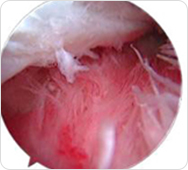

保障股骨头有利生存环境;关节腔内炎症、积液、游离物质若不清理干净,将会进一步侵蚀骨质;

促进新骨再生;股骨头表面的坏死骨剥离后,促进新生骨面接触营养环境,有利骨质的再生。

通过彻底清除关节腔内积液、炎症及游离物质,促进坏死骨质再生,改善跛行、受限症状,避免置换。

通过可视微创针镜,精准定位关节腔内炎症、积液及游离物质位置,有效清理,同时松解关节腔内粘连组织,为股骨头自我修复提供有利环境